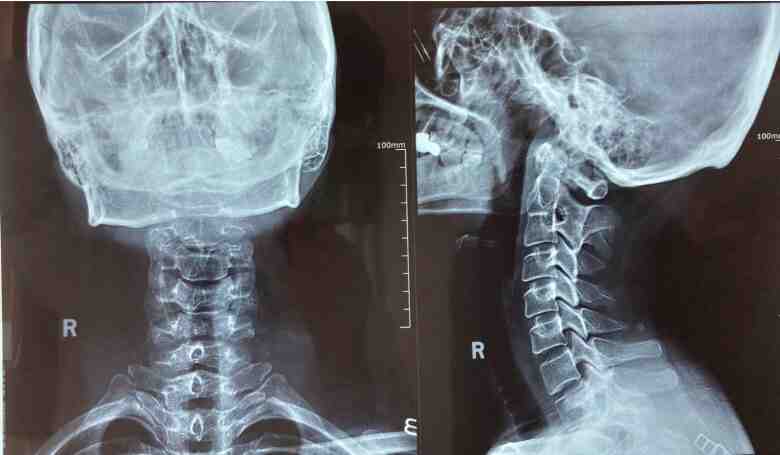

有一天晚上,她洗完脸转身拿毛巾,就觉得天眩地转,墙也晃,棚也晃,灯也晃,直接摔倒在地。儿子打120把她送到医院。最后颈椎CT检测是颈椎有4-5节轻度向后反曲,压迫神经了,用了各种方法治疗,放血疗法,小针刀,效果不明显。办公时间久了,看了一会儿手机,脖子就难受,后来发展到脑供血不足,总昏昏沉沉的。

直到在新闻里看到赵保莲主任赵氏古方疗法的介绍,全面了解后订了一个疗程,使用2天,脖子疼痛感就减轻了,脑袋也清亮了,能大转头了。连续治了二个多月,脖子所有症状全部消失,手也不麻了。到医院拍CT,发现突出和骨刺都没了。有这方面需要的朋友,可以加赵主任微信,希望能对你有所帮助。